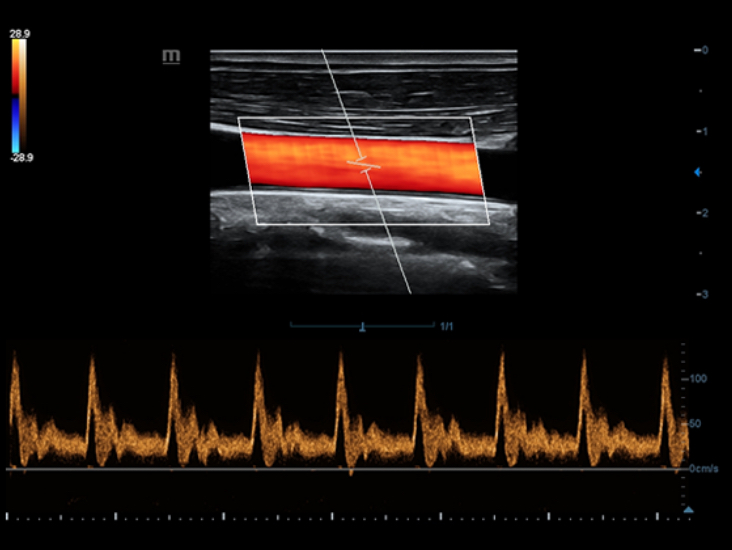

–°–Ņ–Ķ—Ü–ł–į–Ľ–ł–∑–ł—Ä–ĺ–≤–į–Ĺ–Ĺ—č–Ļ —É—Ö–ĺ–ī –Ī–Ľ–į–≥–ĺ–ī–į—Ä—Ź ECHO

–°–ĺ–≤–ľ–Ķ—Ā—ā–Ĺ–ĺ —Ā —Ā–ĺ–≤—Ä–Ķ–ľ–Ķ–Ĺ–Ĺ—č–ľ–ł —É–Ľ—Ć—ā—Ä–į–∑–≤—É–ļ–ĺ–≤—č–ľ–ł —ā–Ķ—Ö–Ĺ–ĺ–Ľ–ĺ–≥–ł—Ź–ľ–ł –Ĺ–ĺ–≤–ĺ–Ķ —Ä–Ķ—ą–Ķ–Ĺ–ł–Ķ –ĺ—ā Mindray –Ņ—Ä–Ķ–ĺ–Ī—Ä–į–∑—É–Ķ—ā –į–ļ—ā—É–į–Ľ—Ć–Ĺ—č–Ķ –∑–į–ī–į—á–ł –ļ–Ľ–ł–Ķ–Ĺ—ā–ĺ–≤ –≤ –ļ–Ľ–ł–Ĺ–ł—á–Ķ—Ā–ļ–ł–Ķ –Ņ–ĺ—ā—Ä–Ķ–Ī–Ĺ–ĺ—Ā—ā–ł. –ü–ĺ—Ā—ā–ĺ—Ź–Ĺ–Ĺ–ĺ —Ä–į–∑–≤–ł–≤–į—Ź—Ā—Ć, —ć—ā–į —Ā–ł—Ā—ā–Ķ–ľ–į —Ā–ĺ—á–Ķ—ā–į–Ķ—ā –≤ —Ā–Ķ–Ī–Ķ —Ā—ā—Ä–Ķ–ľ–Ľ–Ķ–Ĺ–ł–Ķ –ļ –Ĺ–Ķ–ĺ–≥—Ä–į–Ĺ–ł—á–Ķ–Ĺ–Ĺ—č–ľ –≤–ĺ–∑–ľ–ĺ–∂–Ĺ–ĺ—Ā—ā—Ź–ľ –ł –∂–Ķ–Ľ–į–Ĺ–ł–Ķ –∑–į–≥–Ľ—Ź–Ĺ—É—ā—Ć –≤ –Ī—É–ī—É—Č–Ķ–Ķ.

–ú–Ĺ–ĺ–≥–ĺ—Ą—É–Ĺ–ļ—Ü–ł–ĺ–Ĺ–į–Ľ—Ć–Ĺ–į—Ź —Ā–ł—Ā—ā–Ķ–ľ–į DC-60 Exp —Ā X-Insight –Ņ—Ä–Ķ–ī—Ā—ā–į–≤–Ľ—Ź–Ķ—ā —Ā–ĺ–Ī–ĺ–Ļ –ļ–ĺ–ľ–Ņ–Ľ–Ķ–ļ—Ā–Ĺ–ĺ–Ķ —Ä–Ķ—ą–Ķ–Ĺ–ł–Ķ, –ļ–ĺ—ā–ĺ—Ä–ĺ–Ķ –Ņ–ĺ–ľ–ĺ–≥–į–Ķ—ā —É–Ņ—Ä–į–≤–Ľ—Ź—ā—Ć –Ņ–ĺ–≤—Ā–Ķ–ī–Ĺ–Ķ–≤–Ĺ–ĺ–Ļ –ļ–Ľ–ł–Ĺ–ł—á–Ķ—Ā–ļ–ĺ–Ļ –Ņ—Ä–į–ļ—ā–ł–ļ–ĺ–Ļ —Ā –Ľ–Ķ–≥–ļ–ĺ—Ā—ā—Ć—é –ł —É–≤–Ķ—Ä–Ķ–Ĺ–Ĺ–ĺ—Ā—ā—Ć—é.

–ě—Ā–Ĺ–ĺ–≤—č–≤–į—Ź—Ā—Ć –Ĺ–į –≥–Ľ—É–Ī–ĺ–ļ–ĺ–ľ –Ņ–ĺ–Ĺ–ł–ľ–į–Ĺ–ł–ł –Ņ–ĺ—ā—Ä–Ķ–Ī–Ĺ–ĺ—Ā—ā–Ķ–Ļ –ļ–Ľ–ł–Ķ–Ĺ—ā–ĺ–≤, –ļ–ĺ–ľ–Ņ–į–Ĺ–ł—Ź Mindray —Ä–į–∑—Ä–į–Ī–ĺ—ā–į–Ľ–į —Ā–ł—Ā—ā–Ķ–ľ—É DC-60 Exp —Ā X-Insight, —á—ā–ĺ–Ī—č –ĺ–Ī–Ķ—Ā–Ņ–Ķ—á–ł—ā—Ć –≤—č—Ā–ĺ–ļ—É—é –Ņ—Ä–ĺ–ł–∑–≤–ĺ–ī–ł—ā–Ķ–Ľ—Ć–Ĺ–ĺ—Ā—ā—Ć –ł —ā–ĺ—á–Ĺ–ĺ—Ā—ā—Ć –≤–ł–∑—É–į–Ľ–ł–∑–į—Ü–ł–ł –≤–ļ—É–Ņ–Ķ —Ā –Ĺ–į–≥–Ľ—Ź–ī–Ĺ–ĺ—Ā—ā—Ć—é, –ł—Ā–ļ–Ľ—é—á–ł—ā–Ķ–Ľ—Ć–Ĺ–ĺ–Ļ –ł–Ĺ—ā–Ķ–Ľ–Ľ–Ķ–ļ—ā—É–į–Ľ—Ć–Ĺ–ĺ—Ā—ā—Ć—é –ł –ĺ–≥—Ä–ĺ–ľ–Ĺ—č–ľ –ĺ–Ņ—č—ā–ĺ–ľ.